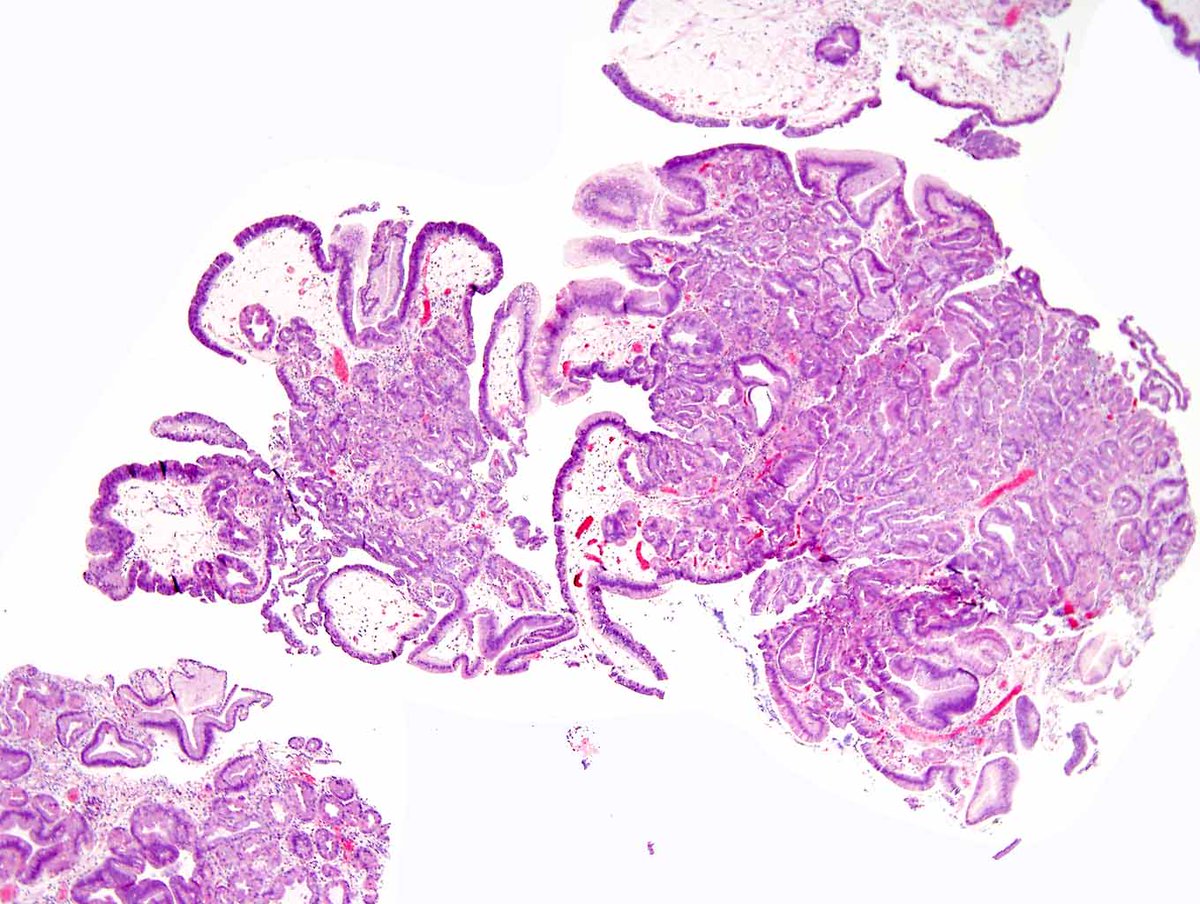

A teaching point from our Editors. How do you distinguish between intrapancreatic bile duct carcinoma and pancreatic ductal carcinoma? Samuel Freire